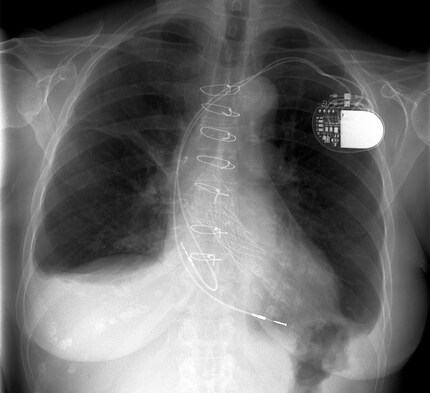

Die Cyborg-Gesellschaft ist eine hoch technologisierte. Das bedingt allem voran grosses Vertrauen des Menschen in die Technologie. Am Beispiel Smartphone mag das etwas lächerlich klingen, nehmen wir aber einen Herzschrittmacher als Beispiel, sieht das schon anders aus. Wenn wir einen Schrittmacher brauchen, müssen wir grosses Vertrauen in dessen Funktionsweise und Tüchtigkeit setzen. Ohne dieses Vertrauen würden sich wohl niemand einen Schrittmacher einsetzen lassen. Auf das Smartphone lässt sich das genauso übertragen, es muss ja nicht gleich um Leben und Tod gehen: Sind wir unterwegs angewiesen auf das Mobiltelefon, müssen wir darauf vertrauen, dass es uns nicht im Stich lässt. Wenn wir beispielsweise auf einen lebensverändernden Anruf warten oder uns irgendwo im nirgendwo verlaufen haben. In diesen Momenten setzen wir enormes Vertrauen in das Wissen, das hinter den Geräten steckt. Die meisten unter uns verstehen die Funktionsweise dieser Technologien nicht oder nicht vollständig. Wir begeben uns in ein Abhängigkeitsverhältnis. Wir sind abhängig von dem Wissen, das in den Technologien steckt. Wenn wir sie verwenden wollen, sind wir sozusagen dazu gezwungen, unser Vertrauen in sie zu stecken. Durch dieses Vertrauen, das wir in das Wissen und damit unsere Mitmenschen stecken, sind wir sehr stark in soziale Prozesse eingebunden.

Das Wissen, das in Cyborg-Technologien steckt, ist Expertenwissen. In den meisten Fällen ist zur Herstellung einer solchen Technologie das Wissen mehrerer Experten notwendig. Das lässt sich am Beispiel des Herzschrittmachers zeigen. Um überhaupt einen Schrittmacher entwickeln zu können, muss das Wissen über das Zusammenspiel von Herzmuskel und Reizleitersystem bestehen. Dann muss der Schrittmacher irgendwie angetrieben werden. Das funktioniert mit einer Lithiumbatterie. Für die Entwicklung dieser ist auch wieder Wissen notwendig. Dann muss auch noch das Gerät an sich entwickelt werden. Da ich kein Spezialist bin, habe ich sicher noch etwas vergessen. Aber das Dargelegte zeigt, dass mehrere Wissenssysteme zusammenkommen, um die Cyborg-Technologie herzustellen. Wir legen unser Vertrauen folglich nicht nur in ein Wissen, sondern in ganze Wissenssysteme und wir vertrauen darauf, dass ihr Zusammenspiel funktioniert. Schliesslich hat nicht jeder Träger eines Herzschrittmachers jederzeit eine Heerschar von Experten um sich, die im Ernstfall sofort reagieren könnten. Wenn wir solche Technologien verwenden, vertrauen wir darauf, dass sie korrekt entwickelt und getestet wurden.

Cyborgs leben in ständiger Gefahr

Mit der Verwendung von komplexer Technologie ist folglich auch immer eine gewisse Gefahr verbunden. Der Herzschrittmacher könnte aussetzen. Cyborg-Technologien zu verwenden ist gefährlich, wir müssen uns auf andere verlassen, dass die Technologien auch sicher sind. Diese Abhängigkeit von Wissenssystemen macht Cyborgs zu höchst sozialen Wesen. Sie sind nicht nur auf Expertenwissen angewiesen, sondern auch auf andere Cyborgs. Die Grenze zwischen Individuum und Gesellschaft verschwimmt immer mehr. Cyborgs sind sich ihrer Abhängigkeit von Wissenssystemen und anderen Cyborgs bewusst. Denn: Im Technologischen steckt auch immer etwas Soziales. Als Cyborgs gehen wir Gefahren ein und geben einen Teil unserer Individualität ab.